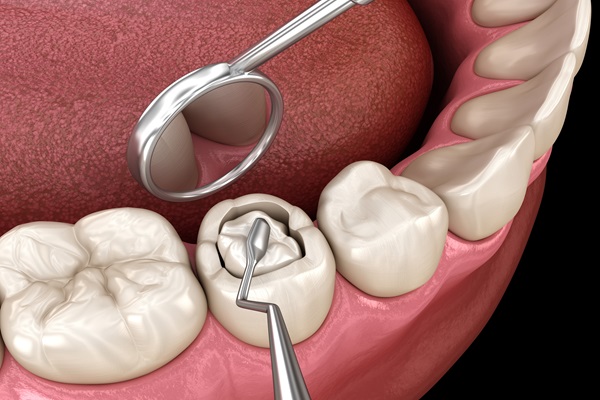

Comprehensive dental care for you and your family